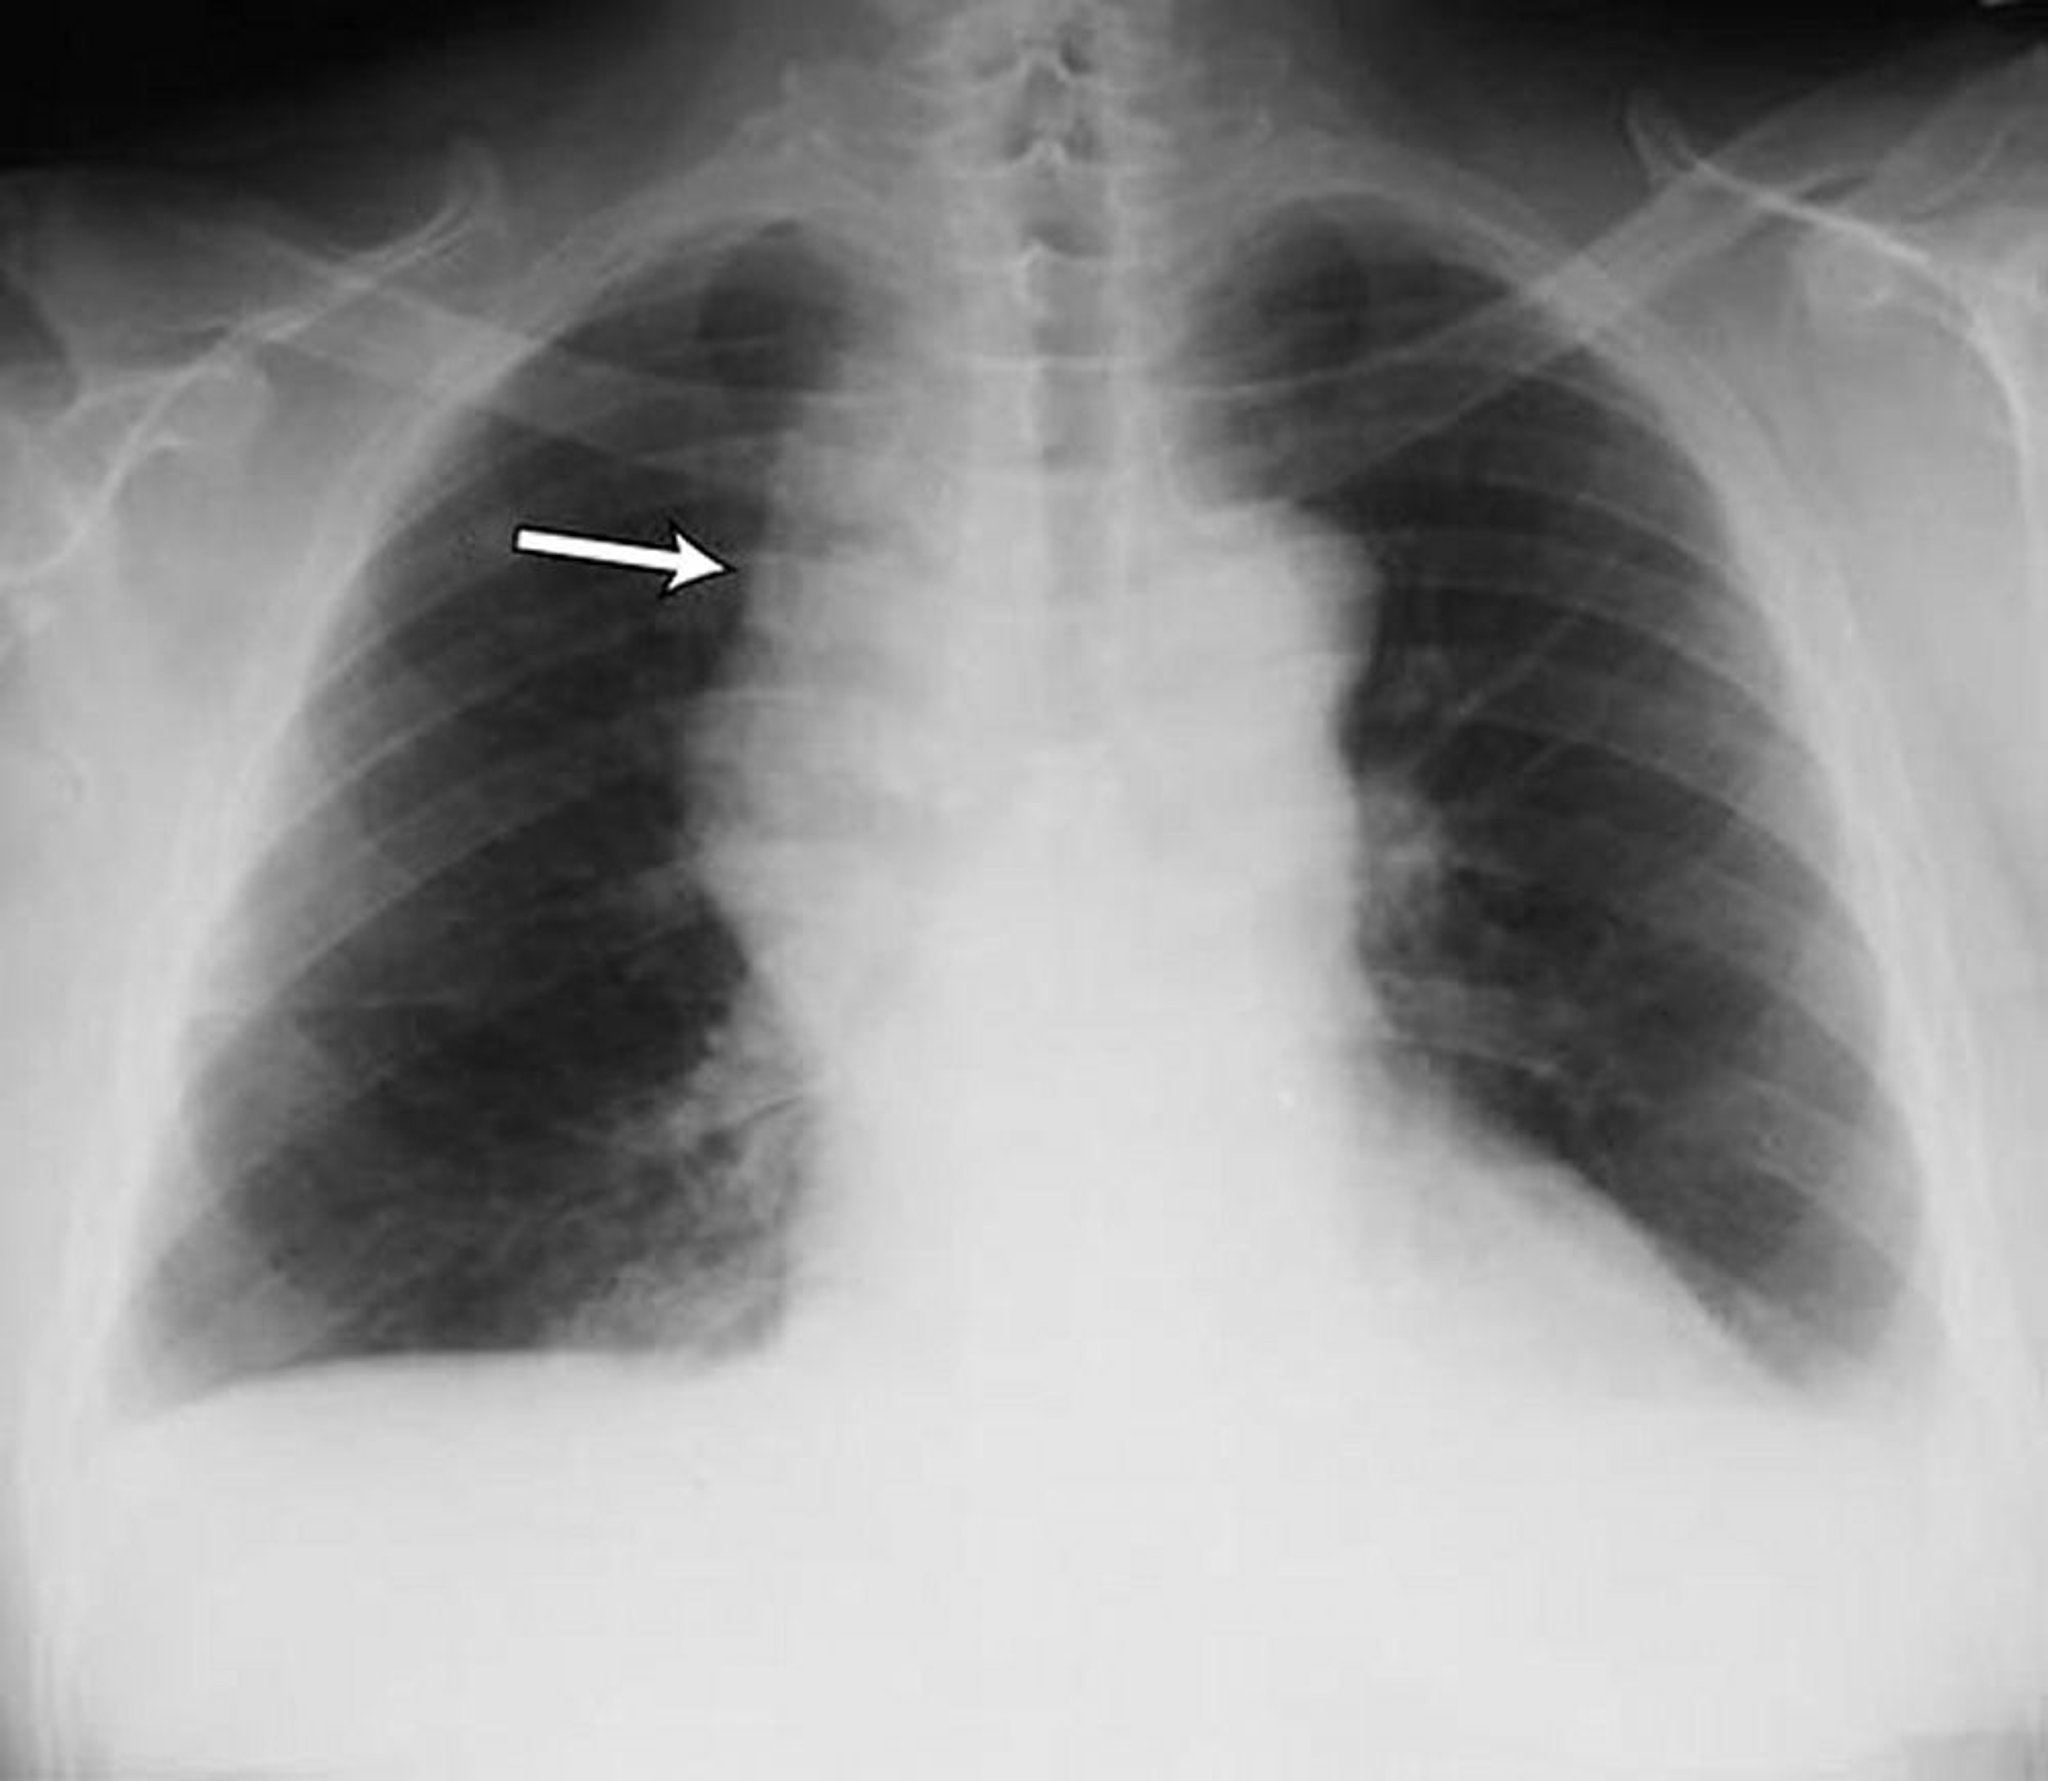

Derrames pleurales bilaterales leves en un paciente con linfoma no Hodgkin. Ambos ángulos costofrénicos están romos. La flecha señala el mediastino dilatado a causa del linfoma.

By permission of the publisher. From Huggins J, Sahn S. In Bone's Atlas of Pulmonary and Critical Care Medicine. Edited by J Crapo. Philadelphia, Current Medicine, 2005.